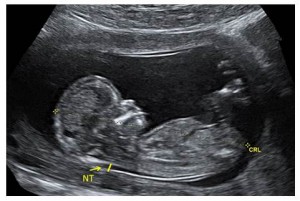

11-14 Week (Nuchal Translucency) Ultrasound

This ultrasound measures the clear (translucent) fluid at the back of the baby's neck. This pocket of fluid is also called the nuchal translucency (NT). It is normal for every baby to have some fluid at the back of the neck at this time.

When a baby has more fluid than what we typically see, it means there is a higher chance for the baby to have a genetic condition or another health issue.

This ultrasound can give you an accurate due date, and can tell you how many babies you are expecting. The ultrasound also looks at the baby's body parts, like the heart and the brain. The baby is still too small at this stage to be able to see the body parts in detail. There may be differences in how the body is growing and developing which cannot be seen at this time, but will be more obvious later in pregnancy at the 18-22 week (detailed anatomy) ultrasound